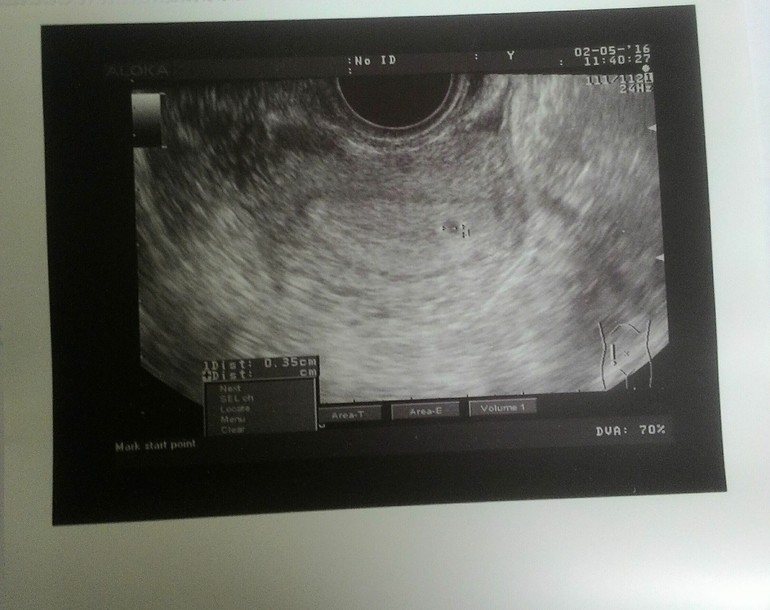

и наша первая встреча, с моей долгожданной, и самой прекрасной точкой !!!

точка, целых 3,5 мм)))